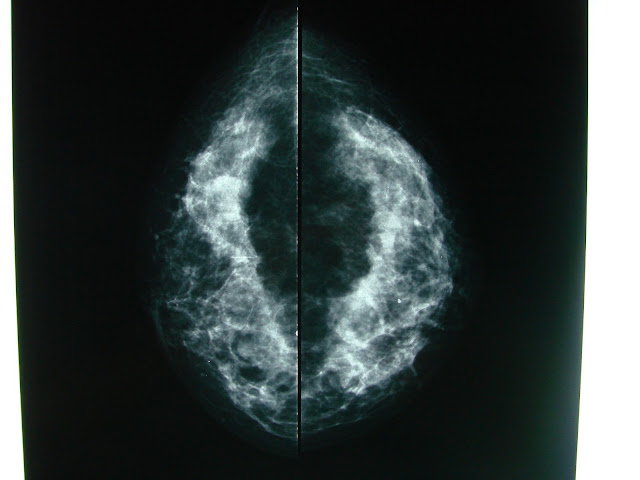

LAST YEAR AUGUST 2012 She said to feel an small asymptomatic irragularity less than 1 cm in her inner quadrant of her remaining RIGHT breast and went for her annual Mammography with these images reported :

Cefalo Caudal View and Close Up , a single Macrocalcification is seen in the INNER QUADRANTS

Slight density near it.

Medio Lateral Oblique View , moderate density , the same macrocalcification and scattered densities

Probably Benign Inflammatory Lymph Nodes

Close up : Macrocalcification associated density.

BACK THEN BIRADS II

Radiologist had no clear information to recommend a COMPLEMENTARY procedure.

NOW IF YOU WERE HER BREAST SURGEON OR ONCOLOGIST WOULD YOU CONCUR?